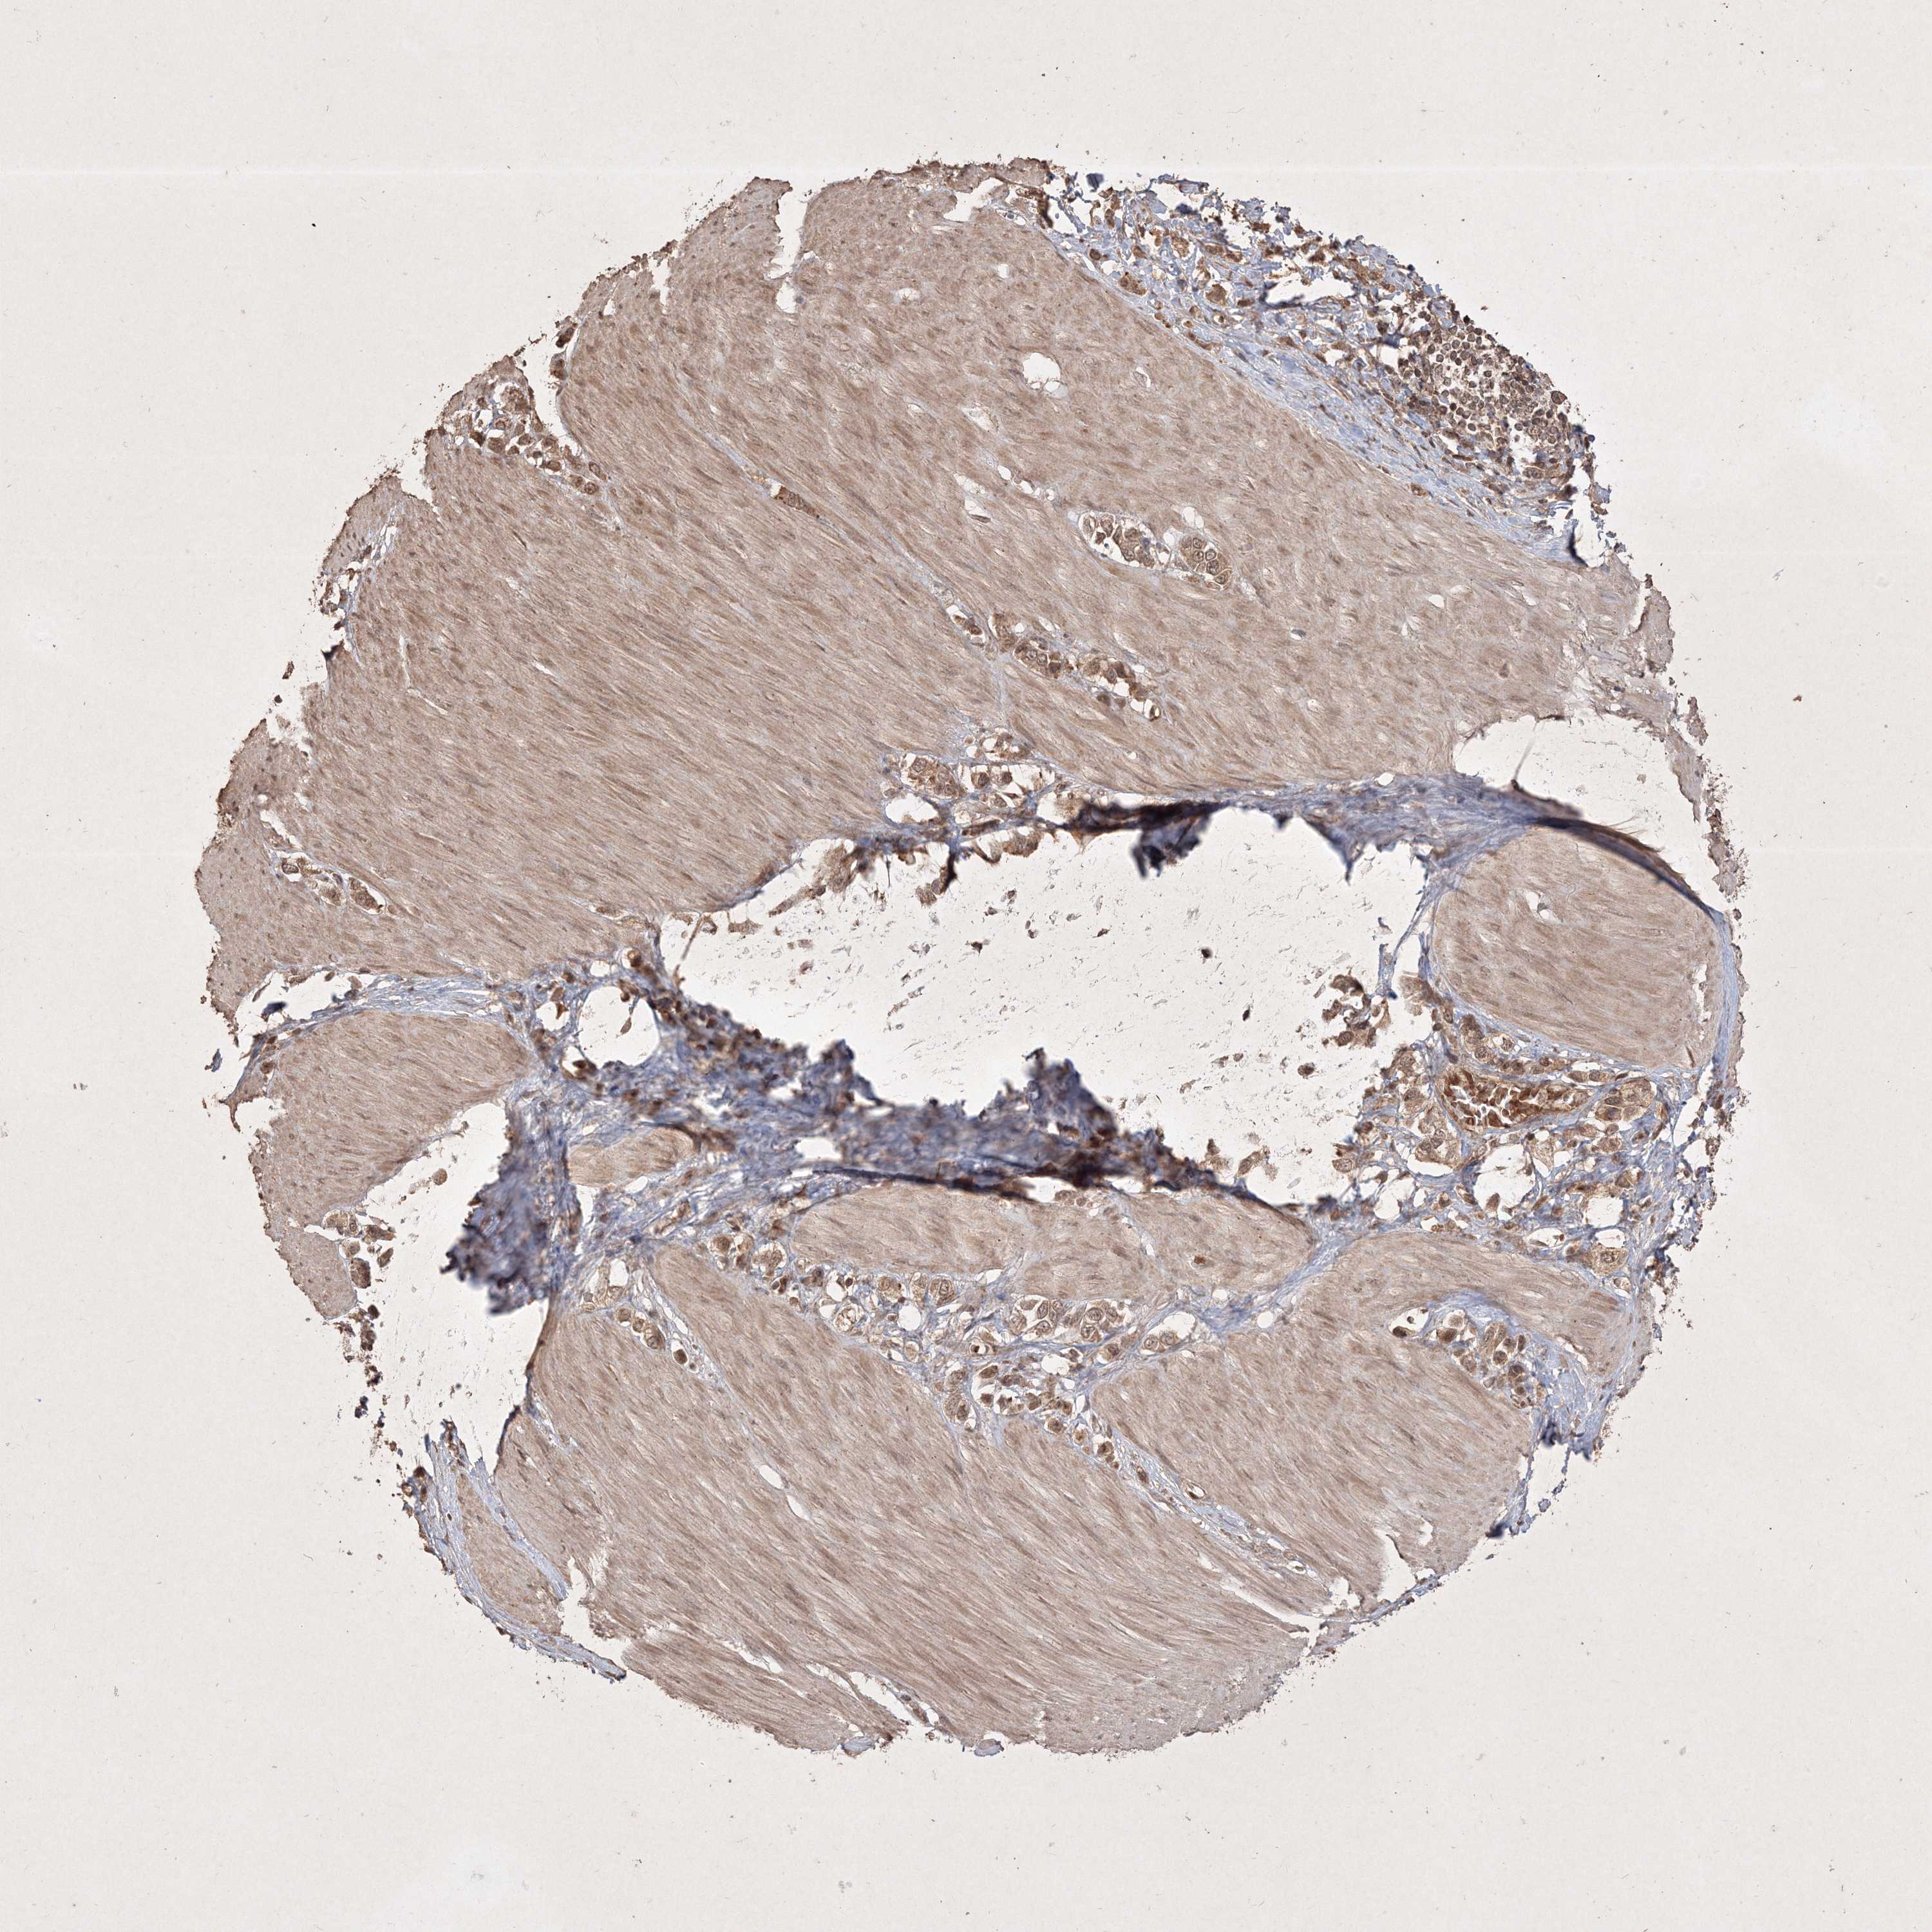

STOMACH CANCER - Protein expressioni

A mouse-over function shows sample information and annotation data. Click on an image to view it in a full screen mode. Samples can be filtered based on level of antibody staining by selecting one or several of the following categories: high, medium, low and not detected. The assay and annotation is described here.

Note that samples used for immunohistochemistry by the Human Protein Atlas do not correspond to samples in the TCGA dataset.

Antibody stainingi

Antibody staining in the annotated cell types in the current human tissue is reported as not detected, low, medium, or high, based on conventional immunohistochemistry profiling in selected tissues. This score is based on the combination of the staining intensity and fraction of stained cells.

Each image is clickable and will lead to virtual microscopy that enables deeper exploration of all samples and also displays staining intensity scores, fraction scores and subcellular localization as well as patient and tissue information for each sample.

Antibody HPA038875

Antibody HPA062281

Antibody CAB033750

Staining

Adenocarcinoma, NOS